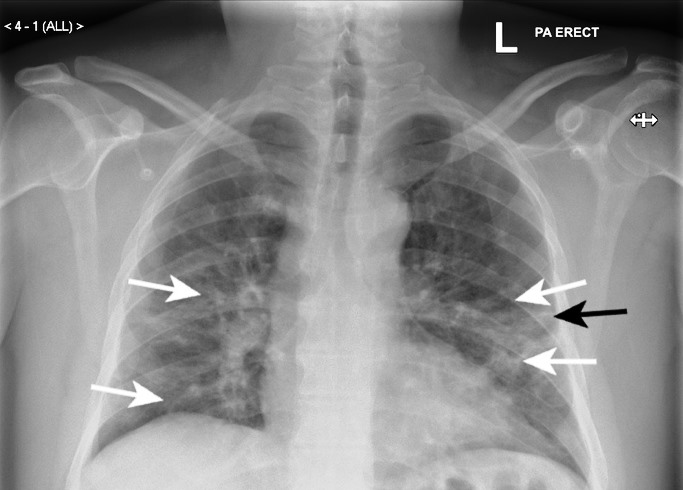

Система машинного обучения была обучена оценивать рентгенограмму грудной клетки для потенциальной диагностики таких состояний, как коллапс легких (спадение доли легкого или ателектаз) и увеличенное сердце (кардиомегалия). При этом система состояла из двух частей: так называемый "классификатор", предназначенный для прогнозирования определенного подмножества задач, и "отбраковщик", который решает, должна ли конкретная задача быть решена его собственным "классификатором", либо человеком.